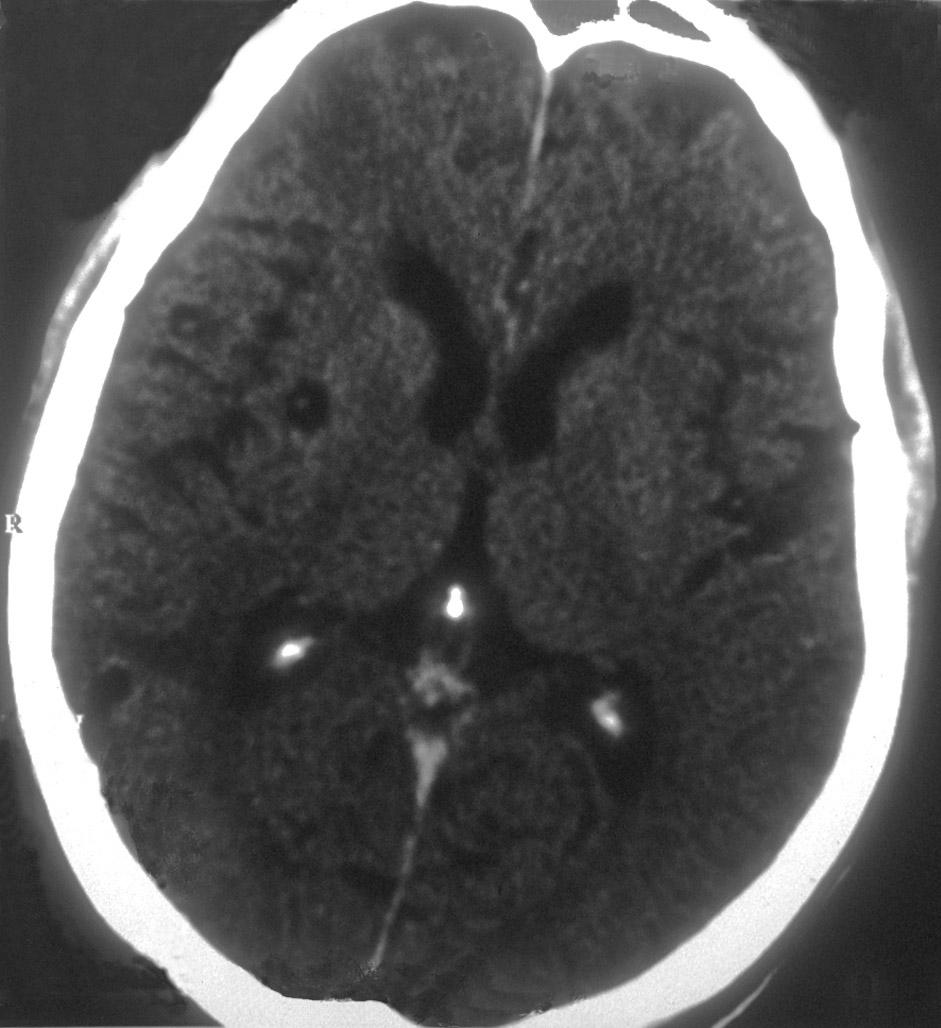

Een 56-jarige Nicaraguaanse man met een blanco voorgeschiedenis werd door een lokale gezondheidsmedewerker verwezen vanwege epilepsie. Heteroanamnestisch bleek het te gaan om een epileptisch insult, hetgeen in de afgelopen maand tweemaal was voorgekomen. Bij het neurologisch onderzoek werden geen afwijkingen gevonden. Gezien het vermoeden van een ruimte-innemend proces werd een CT-scan van de hersenen verricht. Daarbij vielen 5 kleine hypo-intense afwijkingen op.

Wat is uw diagnose?